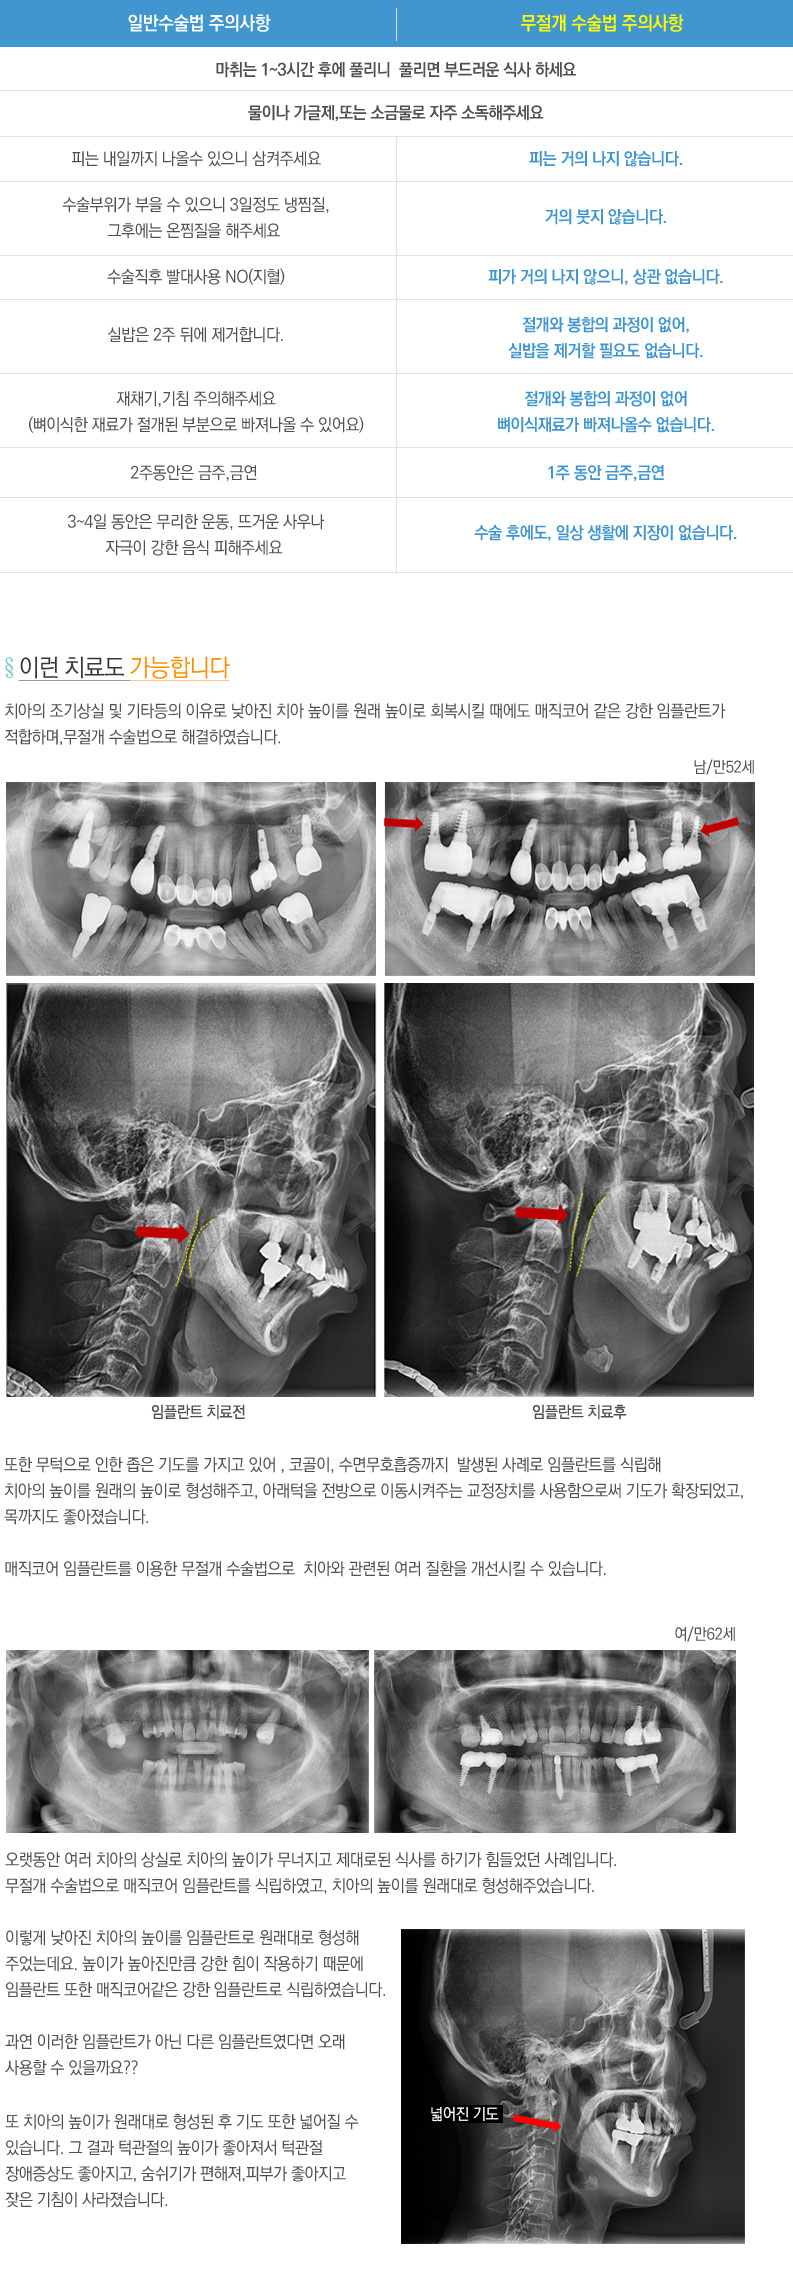

¹«Àý°³ ¼ö¼ú¹ý ½Ã¼ú»ç·Ê

¼÷·ÃµÈ ÀÇ·áÁø°ú dzºÎÇÑ ½Ã¼ú°æÇèÀ» ¹ÙÅÁÀ¸·Î Ä£ÀýÈ÷ ¸ð½Ã°Ú½À´Ï´Ù.

HOME > ÀÓÇöõƮŬ¸®´Ð > ¹«Àý°³ ¼ö¼ú¹ý ½Ã¼ú»ç·Ê